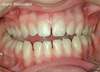

Cas n°2 : Encombrement dentaire sévère

Situation "Avant Traitement": cas d'encombrement dentaire sévère.